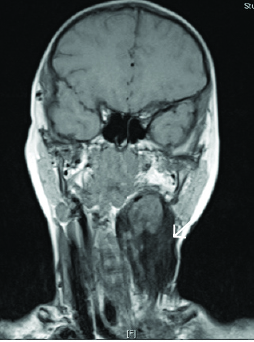

Dermoid cysts are classified by their histologic composition as epidermoid, dermoid, and teratoid cysts. (See Figure 5.) Collectively referred to as dermoid cysts, they can appear in a similar location to thyroglossal duct cysts, although they typically are found in a suprahyoid location rather than the infrahyoid location of thyroglossal duct cysts. However, dermoid cysts tend to form later, appearing more commonly in late childhood or early adulthood, as a result of their slow-growing nature. Pregnancy is associated with increased growth of dermoid cysts.31 Unlike the thyroglossal duct cyst, dermoid cysts do not move when the tongue is protruded.

Figure 5. Patient with Large Left-Sided Dermoid Cyst on MRI |

Image courtesy of Derya Caglar, MD. |